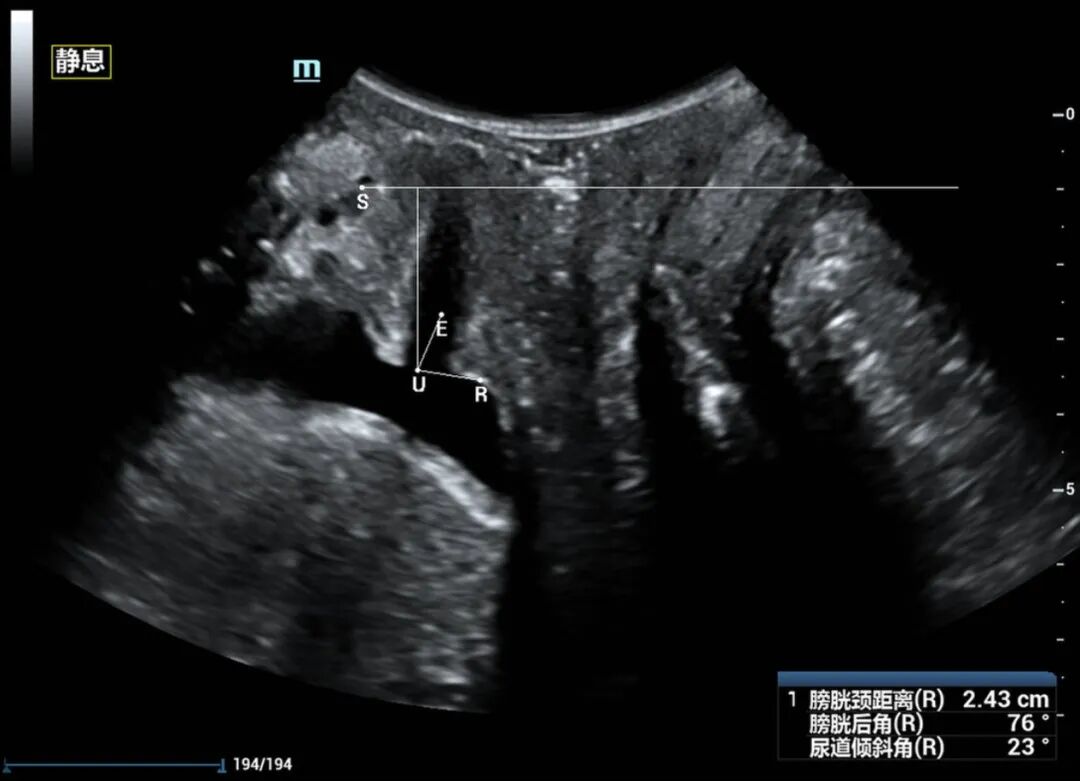

近日,54岁的黄女士因“尿失禁13年”来我院妇女保健科就诊,黄女士讲述了近十年来经常发生尿频尿急憋不住尿的经历,自己咳嗽、大笑或者长时间走路后便出现漏尿等尴尬症状,严重影响正常生活和社交活动。由于涉及隐私部位,怕人笑话,一开始她不敢跟身边的人说起这件事,能忍则忍。最近随着症状加重,难以忍受,终于来我院就诊。 在妇女保健科医师颜惠芳建议下,黄女士前往我院超声医学科行四维盆底超声检查,检查后发现黄女士有膀胱脱垂、子宫脱垂的现象,诊断为“压力性尿失禁”,终于找到漏尿的原因了,黄女士的治疗也可以针对性开展。 现实生活中,不少女性朋友也有过这样尴尬的经历,大笑、打喷嚏、咳嗽时尿液溢出外出时总想找厕所,私密处总有异物感,腰酸背痛,下腹坠胀,夫妻生活不和谐……种种难言之隐羞于说出口,却又如影随形。这一切的罪魁祸首很可能是——盆底功能障碍。 一、什么是盆底功能障碍 盆底功能障碍是指盆底肌肉、筋膜、韧带等支持结构受损而导致的一系列临床症候群,如压力性尿失禁、子宫等盆腔脏器脱垂、粪失禁、梗阻型便秘和性功能障碍等。妊娠和分娩是造成此病的首要原因,其中以经阴道分娩危险性最高,当前已成为影响全球妇女身心健康的五种最常见疾病之一,被称为“社交癌”。 二、为什么会发生盆底功能障碍? 怀孕、分娩、衰老、肥胖、长期便秘、慢性咳嗽、长期提重物等原因,都会导致盆底肌损伤,分娩是造成盆底肌损伤的主要原因。 通常胎儿头部大小都会大于正常的阴道大小,分娩时,阴道会受到胎儿头部的挤压而扩张,造成盆底肌肉损伤。双胎、巨大儿、分娩两次及以上的妈妈们,盆底肌受到的损伤通常会加倍。产后和围绝经期为高发期,被称为严重影响女性生活质量的五大慢性病之一。 三、什么是盆底超声? 盆底超声是使用特殊配置的超声仪器,利用二维图像、三维重建、动态四维显示联合应用,在患者静息、缩肛、valsalva不同状态下,直观了解盆底的静态、动态结构、显示耻骨联合、尿道、膀胱、阴道、宫颈、直肠壶腹及肛管等结构,从而评估盆底各脏器位置、功能,脏器脱垂情况、盆底肌有无损伤等。 盆底超声适应症: 1.盆腔脏器脱垂:膀胱脱垂、子宫脱垂、直肠膨出等; 2.排尿异常:压力性尿失禁、尿潴留、排尿困难等; 3.排便异常:粪失禁、便秘等; 4.性功能障碍:性交痛、性欲降低等; 5.慢性盆腔痛:下腹部疼痛、腰骶部或会阴痛等; 6.产后女性(42天至6个月)盆底功能障碍的早期筛查。 可疑盆底功能障碍性疾病人群、产后复查及围绝经期女性均建议行盆底超声检查。 超声医学科盆底超声检查介绍 我院超声科自2019年开展该项技术以来,已为500余名女性患者完成盆底超声检查。竭诚欢迎有需要的女性市民朋友来电咨询(025-56232058)或前往我院妇女保健科门诊就诊。 盆底超声检查时间:每周一和周二下午(具体以预约安排为准) 盆底超声检查医师简介 褚爱萍 科室副主任,主任医师(资格)。南京超声学会介入与腹部学组委员,从事超声诊断十余年,曾先后于江苏省人民医院及中大医院进修学习,并承担临床教学工作多年,擅长心脏、血管等超声诊断,对腹部、妇产、盆底、浅表、肌骨等亦有丰富的超声诊断经验。 汪金 中国共产党员,副主任医师,医学硕士,先后在四川大学华西医院、重庆医科大学附属儿童医院、北京301医院、朝阳医院等多家三甲医院进修、培训学习,取得了超声产前筛查、盆底超声、输卵管超声造影、肿瘤消融治疗等多项技术资质。 获省妇幼新技术引进三等奖,主持及参与省市级课题3项,发表论文数篇,其中SCI 3篇,授权国家专利9项。 钱露 副主任医师(资格),硕士研究生。毕业于徐州医科大学医学影像专业。从事超声诊断工作十余年,熟练掌握各种常见病、多发病的超声诊断,擅长妇科超声、盆底超声、产前筛查超声等工作。 李诺 主治医师,毕业于徐州医科大学临床医学专业,从事超声诊断工作数年,熟练掌握各种常见病,多发病的超声诊断工作,擅长妇科超声,盆底超声等超声诊断工作。